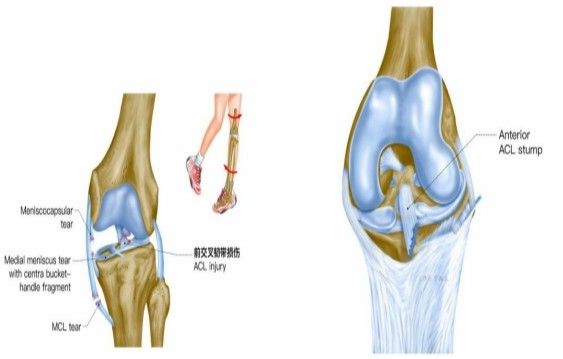

我院骨科三病區(qū)近期收治了4名膝關節(jié)交叉韌帶損傷患者。25歲的齊先生,因打籃球時不慎扭傷左膝,致右膝腫痛,遂來我院治療;30歲趙先生酷愛足球,扭傷右膝關節(jié)來我院就診;50歲的張先生、42歲劉先生因騎車滑倒摔傷、膝關節(jié)腫痛不適、活動受限,收治入院。骨科三病區(qū)李鵬主任團隊詳細查體以及完善影像學檢查后進行診斷:幾位患者共同診斷均有“前交叉韌帶損傷”,不同程度合并有“半月板損傷”、“股骨軟骨損傷”、“內(nèi)側副韌帶斷裂”。

在與患者溝通時,李鵬主任表示:“鑒于年輕患者后期對運動要求高,恢復前交叉韌帶解剖和生理功能極其重要,同時考慮早期功能的鍛煉和美觀程度,建議行關節(jié)鏡微創(chuàng)手術。該手術沒有傳統(tǒng)“開刀”的恐懼不安,有的只是術后的快速康復和手術部位幾處微不可見的小疤痕?!?

經(jīng)患者同意后,李鵬主任手術團隊制定詳細手術方案。手術如期進行,經(jīng)團隊密切配合,對幾位患者分別順利完成關節(jié)鏡下膝關節(jié)鏡鏡檢、關節(jié)清理、股薄肌半腱肌取腱移植術、前交叉韌帶重建術、軟骨損傷微骨折術、半月板縫合修整術等。